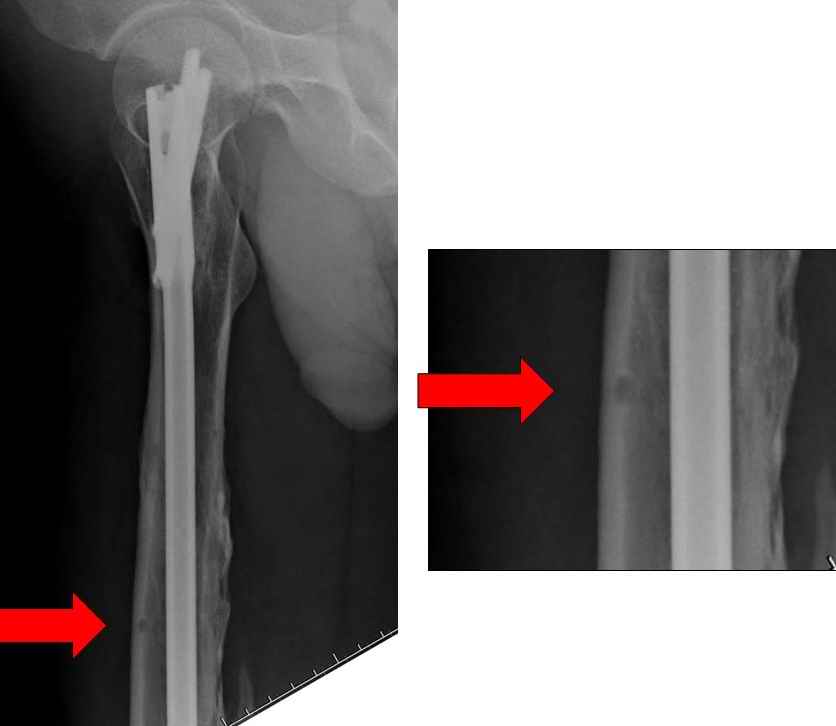

На снимке N2 виден канал от стержня во фронтальной плоскости, на уровне которого на снимке N7 уже перелом.

>“На представленных R-граммах нет снимков с АВФ. На снимке №4

>дистальный статический винт не доходит до второго кортикала “

Снимок №4 сделан после несостоятельности интрамедуллярного штифта, осложнения инфекцией канала и после миграции шурупов. Я имел ввиду, что снимок № 2 после удаления наружного фиксатора в интрамедуллярном варианте, на увеличенном снимке дырка на переднем кортексе (см. снимок) stress zone Чтобы правильно без осложнений провести half pins, необходимо соблюсти нескольких правил, во первых, они должны вводится в середине диаметра кости с предварительным просверливанием. Во время просверливания кости, сверло проходит первый, потом второй дальний кортекс и стержен вводится вручную. А иногда сверление проходит по касательной к кортексу, нагреваются местные ткани, создается ожог и локальный некроз. Или как будто делается кортикотомия с помощью сверла, как при

методе Илизарова, ослабляя кортикальный слой. Создается стрессовая зона, которая при незначительной травме может осложниться стрессовым

переломом.